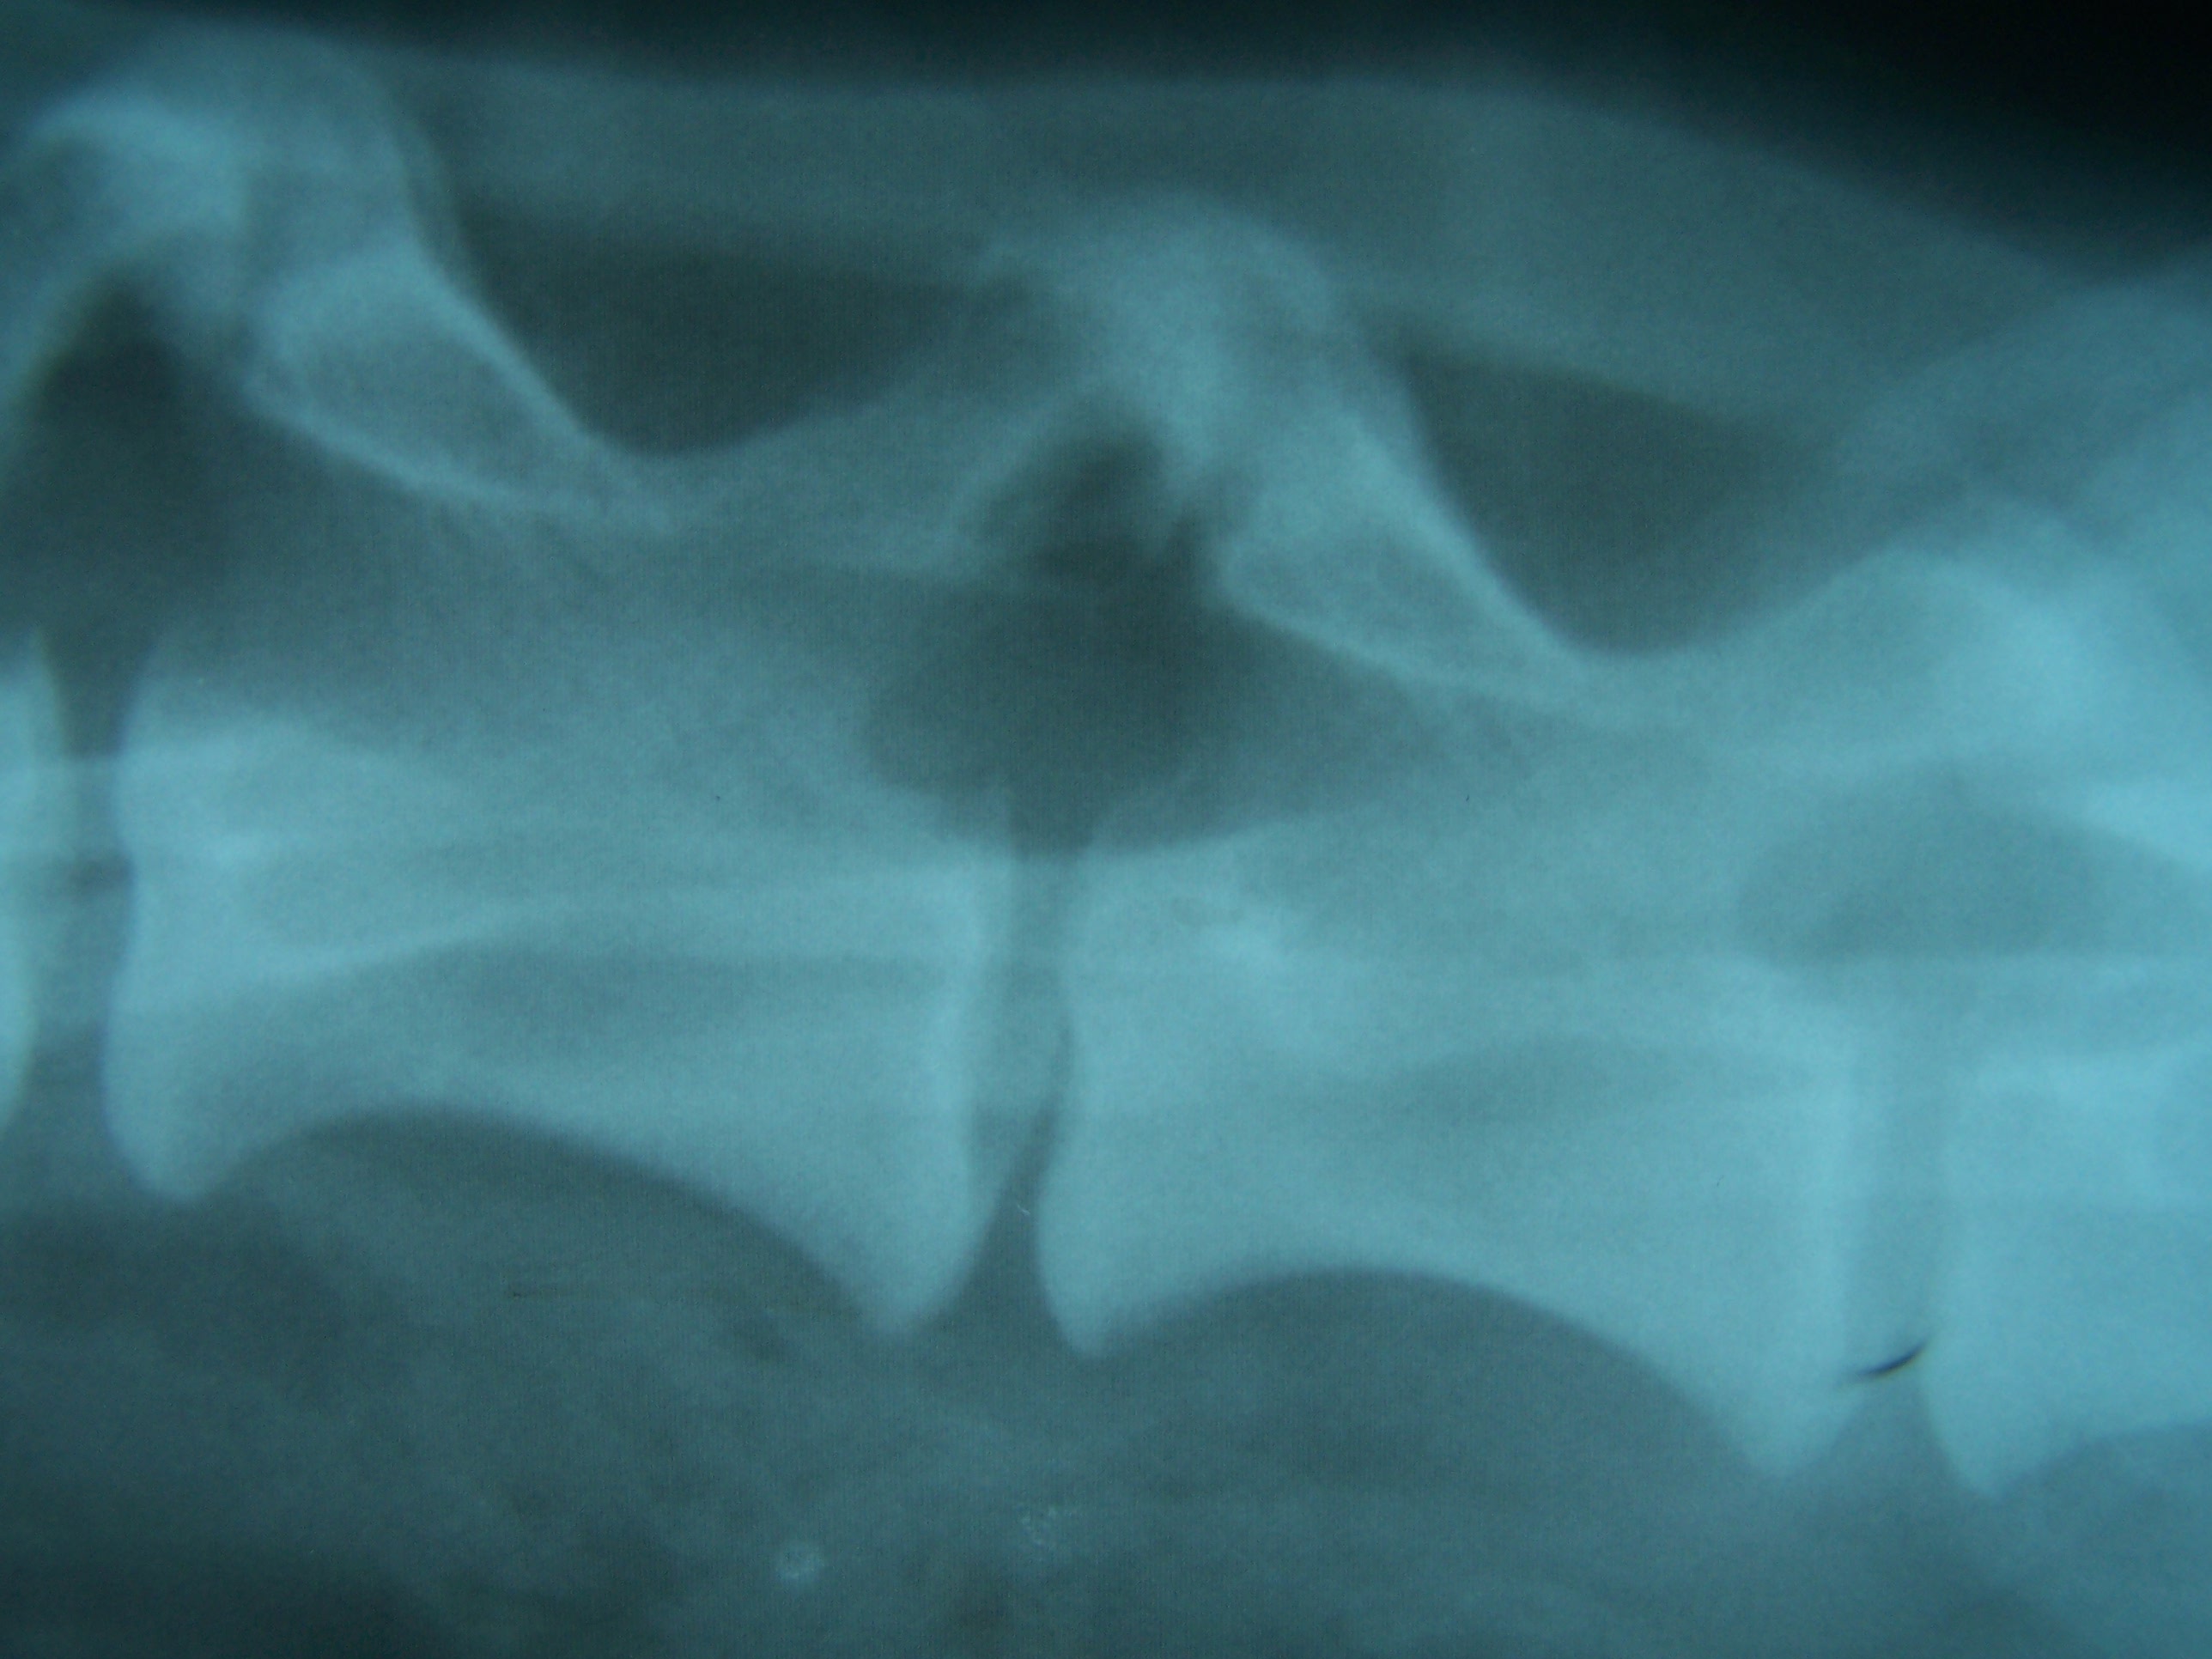

A diagnózis felállítása radiológiai vizsgálattal lehetséges. Általában már az érintett szakaszról készített tájékozódó röntgenfelvételen látható a csigolyák közötti ízületi nyúlványok degeneratív elváltozása.

Myelographiát minden esetben végeznek a betegség feltérképezésekor, hiszen a gerincvelő összenyomódásának mértéke csak így térképezhető fel pontosan, ami szükséges a gyógykezelés megtervezéséhez. Néhány

esetben szükség lehet CT esetleg MRI vizsgálatra ez azonban ritkán fordul elő.